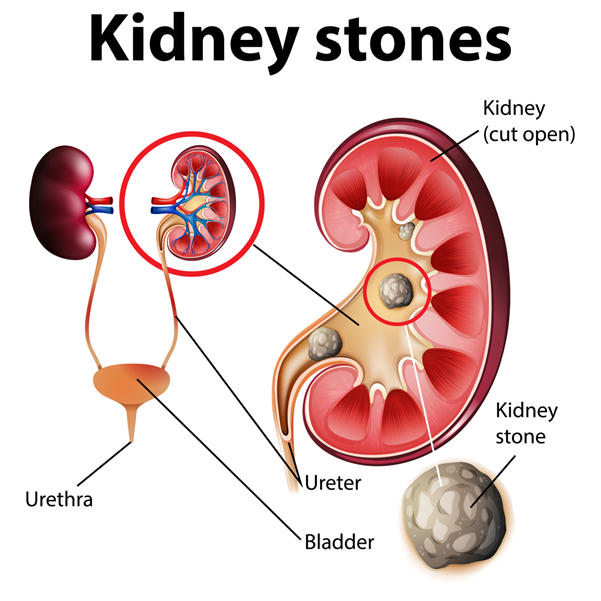

Kidney Stones: A Painful Reminder from Within

Introduction: Kidney stones, those tiny but mighty mineral deposits formed within our kidneys, have been causing havoc in the human body for centuries. From their

Coping with Kidney Stones: Causes, Symptoms, and Treatment

Kidney stones can be a painful and uncomfortable experience for anyone who suffers from them. Kidney stones are small, hard mineral deposits that form in